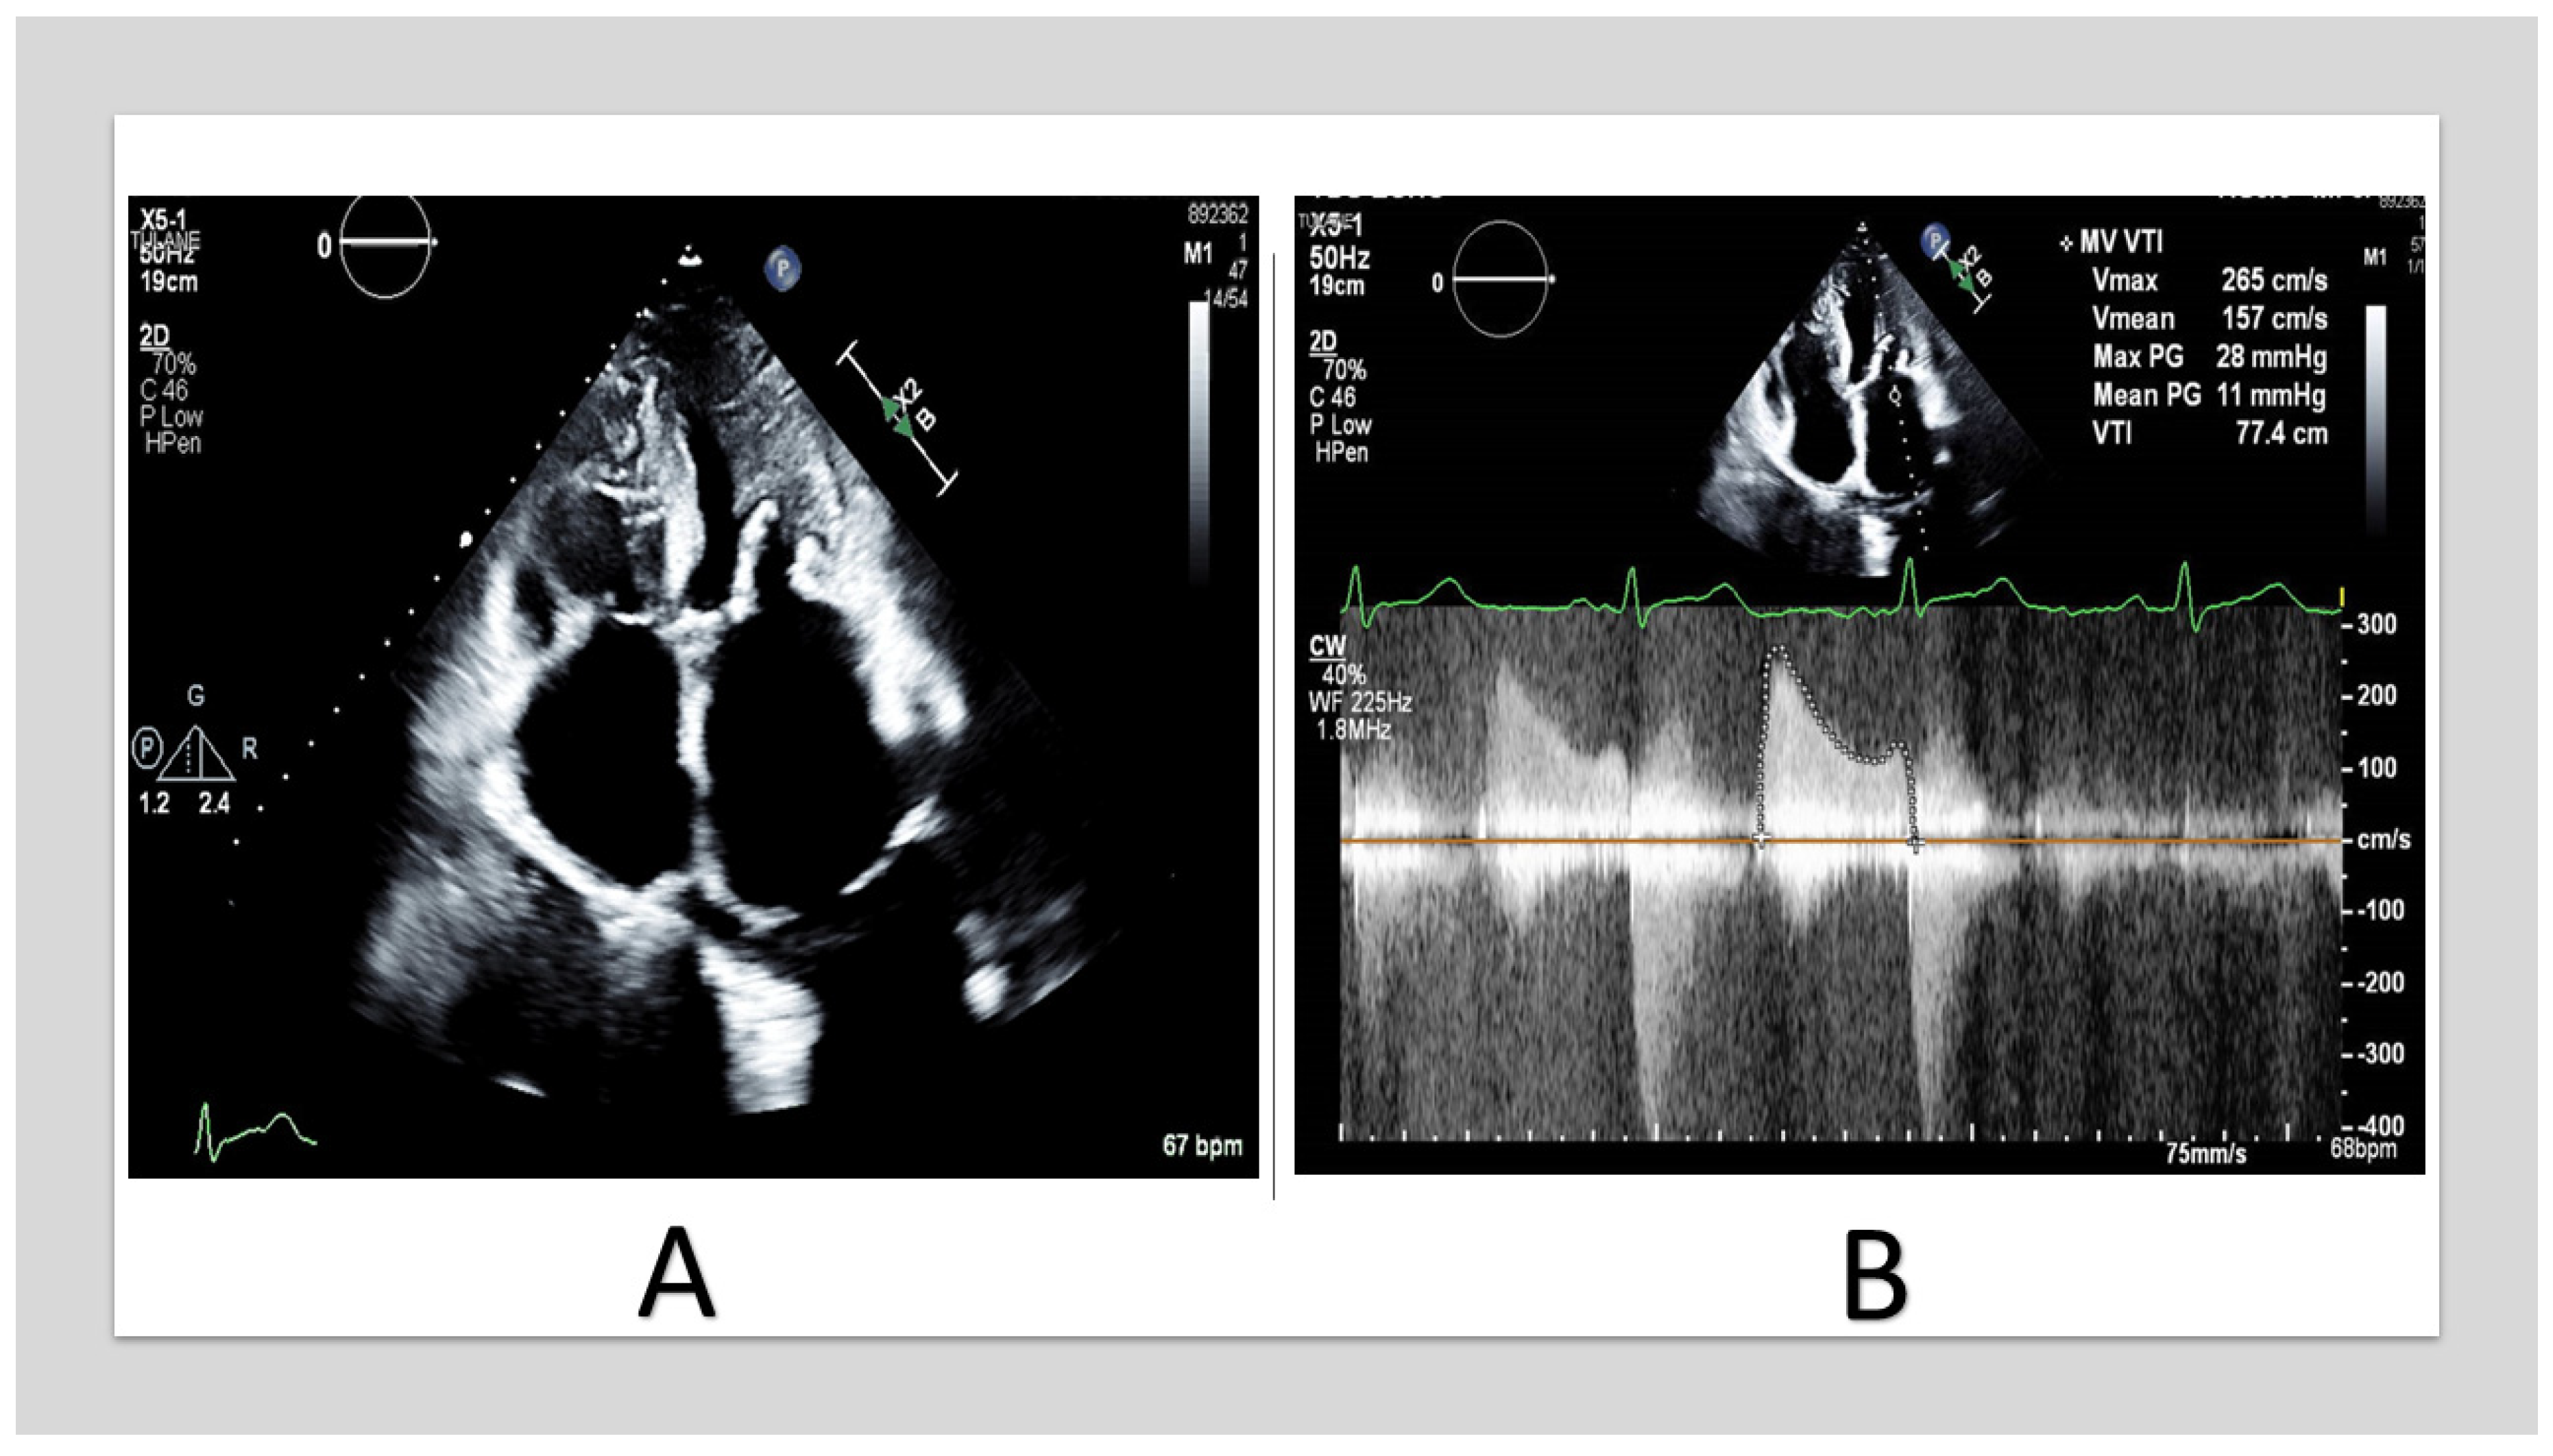

On the other hand, MS is primarily due to the annular calcium shelf displacing the valve annulus inward along with calcifications extending toward the base of the leaflets, resulting in inflow obstruction [21] (Figure 3 and Figure 4). Involvement of the anterior annulus is a key contributor to the development of MS [19]. Unlike rheumatic MS (RMS), where the obstruction is at the tip of the leaflets, the obstruction is at the annulus base of the leaflets in degenerative MS. Furthermore, the calcification is non-planar and results in tubular inflow, unlike the funnel shape in RMS [19].

TTE of 57_year_old woman with end-stage renal disease. (A) shows severe MAC involving the anterior and the posterior annulus with extension to the leaflets and the chordae. (B) shows mitral inflow continuous-wave Doppler with mean gradient of 11 mmHg. (TTE: transthoracic echocardiography, MAC: mitral annular calcification).